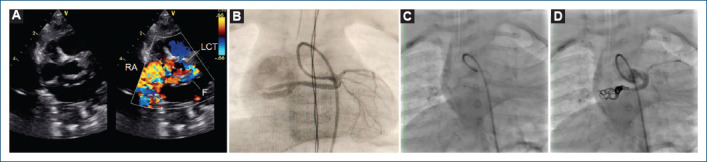

[Endovascular closure of coronary fistula in the infant].

{"title":"[Endovascular closure of coronary fistula in the infant].","authors":"Justo J Santiago-Peña, José F Saaibi-Solano, Andrés F Rubio-Duarte, Iván A Pinto-Martínez, Yudisay Molina-Mora, María I Díaz-Caraballo","doi":"10.24875/ACM.23000216","DOIUrl":null,"url":null,"abstract":"","PeriodicalId":93885,"journal":{"name":"Archivos de cardiologia de Mexico","volume":" ","pages":"515-518"},"PeriodicalIF":0.0000,"publicationDate":"2024-05-08","publicationTypes":"Journal Article","fieldsOfStudy":null,"isOpenAccess":false,"openAccessPdf":"https://www.ncbi.nlm.nih.gov/pmc/articles/PMC12148545/pdf/","citationCount":"0","resultStr":null,"platform":"Semanticscholar","paperid":null,"PeriodicalName":"Archivos de cardiologia de Mexico","FirstCategoryId":"1085","ListUrlMain":"https://doi.org/10.24875/ACM.23000216","RegionNum":0,"RegionCategory":null,"ArticlePicture":[],"TitleCN":null,"AbstractTextCN":null,"PMCID":null,"EPubDate":"","PubModel":"","JCR":"","JCRName":"","Score":null,"Total":0}